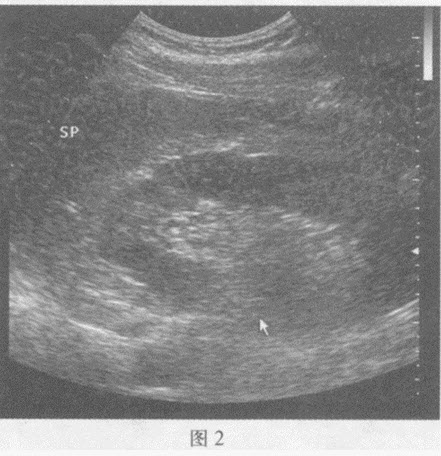

请回答图1、图2箭头所指部位的脏器名称()

A . 图1:左肾;图2:右肾

B . 图1:右肾;图2:左肾

C . 图1:肝脏;图2:脾脏

D . 图1:右肾门;图2:左输尿管

[单选题]请回答图1、图2箭头所指部位的脏器名称:A.图1:左肾;图2:右肾B.图1:右肾;图2:左肾C.图1:肝脏;图2:脾脏D.图1:右肾门;图2:左输尿管